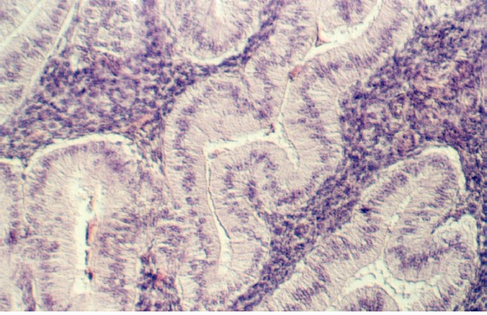

Slide 86 shows a uterus in the proliferative phase. The endometrium is illustrated in the photograph below. Note that the cells are low columnar to high columnar. The glands are relatively straight with a narrow lumina. Outside the glands is the highly cellular lamina propria. The following photos illustrate the proliferative phase with higher magnifications.

After ovulation, the uterine lining becomes more tortuous. The lining is now under the control of progesterone. This steroid hormone stimulates the lining to secrete material that may help nourish both sperm and a potential pregnancy. The glands expand and the lumina are wide and contain products of secretion. The glandular epithelium may be characterized by a droplet of secretory material under the nucleus (near the base) about 2 days after ovulation (day 16). Then, the secretory products move more towards the lumen. Slide 87 shows the Secretory phase of the uterine lining. Note the sections showing coiled or tortuous glands and the dense lamina propria.